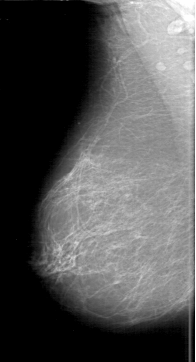

D_4189_1.RIGHT_MLO

LEFT_MLO LINES 6421 PIXELS_PER_LINE 3676 BITS_PER_PIXEL 12 RESOLUTION 43.5 OVERLAY